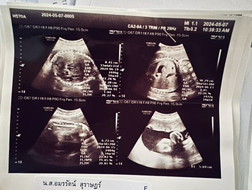

ภาพนี้ตอน13+5ตอนนี้24+1แล้วคะ ผู้ชาย